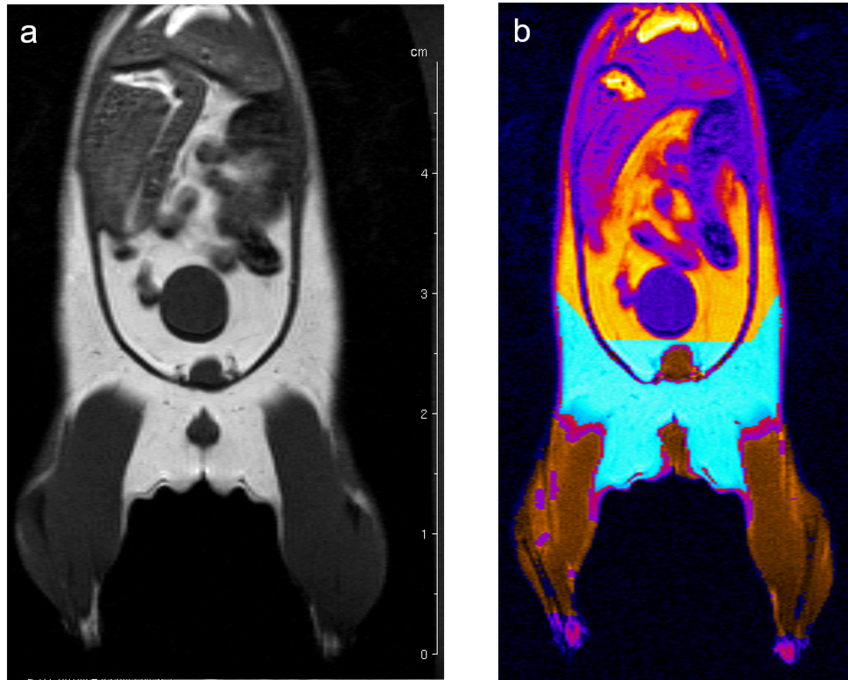

Fat, muscle, tissue-free fluids, and bones generate different signals in response to various radio frequency pulses at distinct magnetic fields, due to their different relaxation properties. We perform MRI studies on mouse using T1-weighted multi-slice-multi-echo (MSME) pulse sequences and analyze the volume of muscle and fat in a well defined and comparable area of the mouse Fig. 6.

Fig. 6: Determination of body fat in mouse. (a) A MSME sequence with a repetition time of 452 ms, echo time of 8.6 ms, field of view 7.0x7.0 cm2 covering the entire body and lower legs, a matrix of 512x256 and slice thickness of 1.0 mm was used to acquire 20 coronal slices with1.0 mm slice thickness and 1.0 mm interslice distance. (b) After evaluation the region in cyan represents the quantified fat and the region in brown the quantified muscle volume.